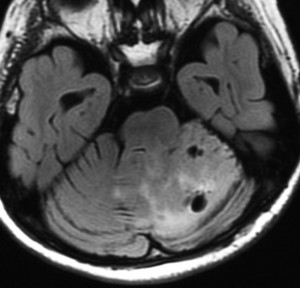

- MRIで確定診断ができます

- MRIで片方の小脳に大きな腫瘍がみられます

- T1強調画像で低信号,T2強調画像でやや高信号になります

- ガドリニウムで増強されないこともありますが,一部が増強されることがあります

- かつては,a cerebellum in the cerebellumといわれたように,小脳の中に別な小脳ができたような形態を示します

- gyriform pattern, laminated lesion, striated appearance, tiger-stripe appearance と表現される所見で診断がつきます

1歳で水頭症と左聴力低下で発症した例

水頭症による嘔吐と軽度の意識障害で発症しました。治療は左小脳橋角部で脳神経を圧迫している部分だけをほんの少し部分摘出しました。水頭症は内視鏡による第3脳室開窓術で治しました。